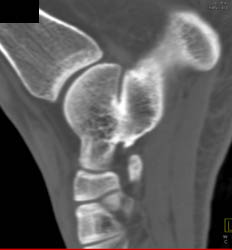

Hematoma in Marrow